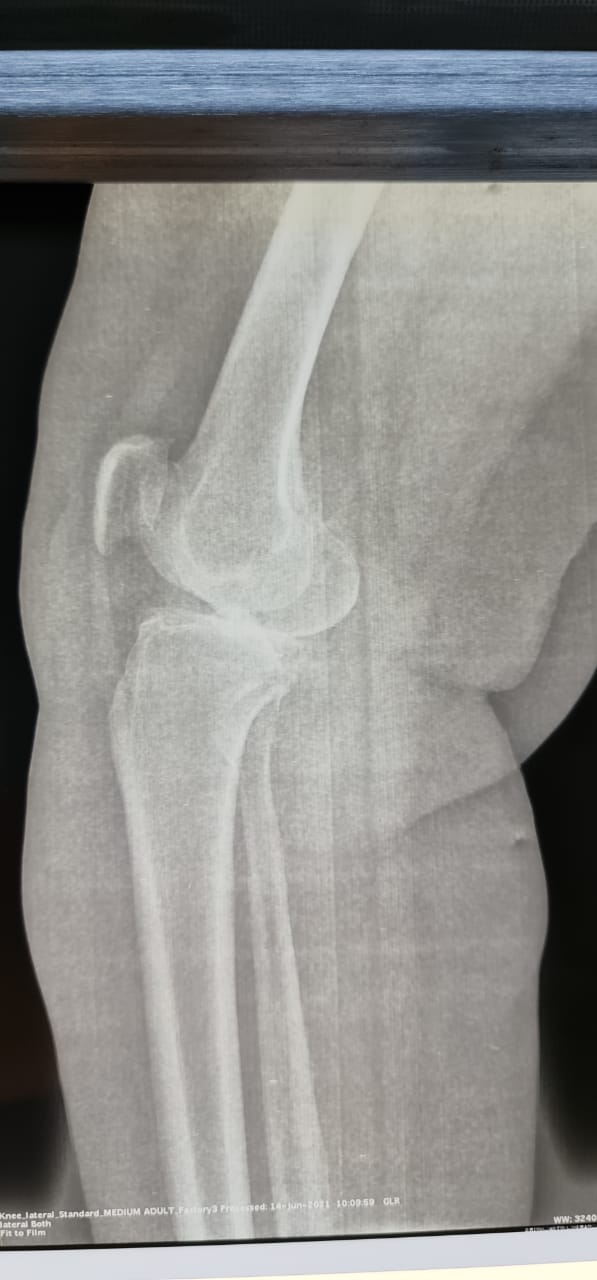

نجح فريق طبي بمستشفى حريملاء العام في إنهاء معاناة مريضة سعودية عمرها ٦٤ سنة تعاني من احتكاك شديد وخشونة بالركبة اليمنى من الدرجة الرابعة .

وأوضحت “صحة الرياض” ، أن المريضة كانت تعاني أيضاً من تآكل كامل بالغضاريف وإنحراف داخلي بالساق ، وصعوبة بالمشي والحركة.